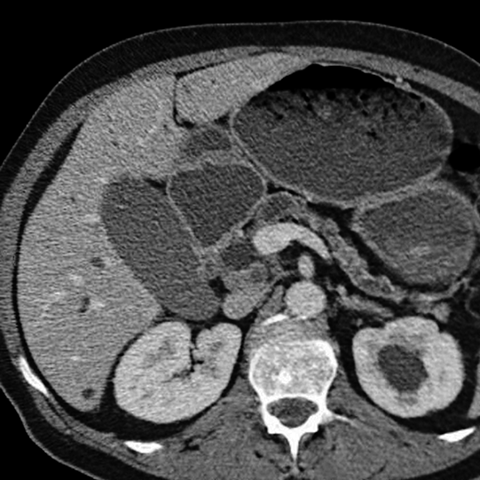

56 year-old male with painless jaundice [4 of 4]